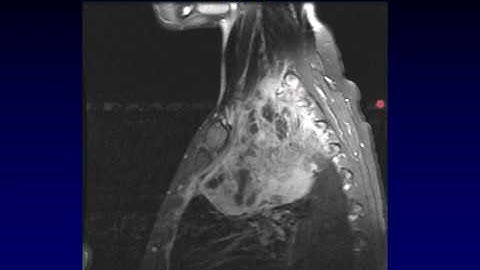

Brachial Plexus part 2